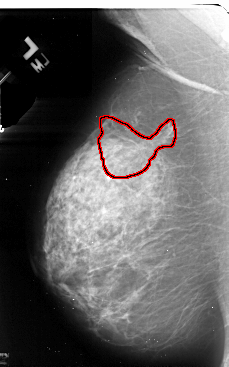

A_1078_1.LEFT_CC

LEFT_CC LINES 5461 PIXELS_PER_LINE 3211 BITS_PER_PIXEL 16 RESOLUTION 42 OVERLAY

FILE: A_1078_1.LEFT_CC.OVERLAY

TOTAL_ABNORMALITIES 1

ABNORMALITY 1

LESION_TYPE MASS SHAPE ARCHITECTURAL_DISTORTION MARGINS SPICULATED

ASSESSMENT 5

SUBTLETY 2

PATHOLOGY MALIGNANT

TOTAL_OUTLINES 2

BOUNDARY

CORE